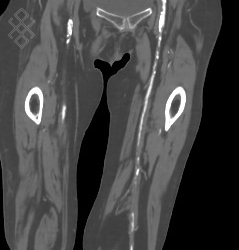

Angioscanner des Membres inférieurs

La durée moyenne de l'examen est de 15 min. En cours d'examen, vous recevrez une injection du produit de contraste. En fonction des personnes, celle-ci peut engendrer une sensation de goût métallique dans la bouche ou de chaleur dans le cou ou entre les jambes. Cette sensation disparaît très rapidement.